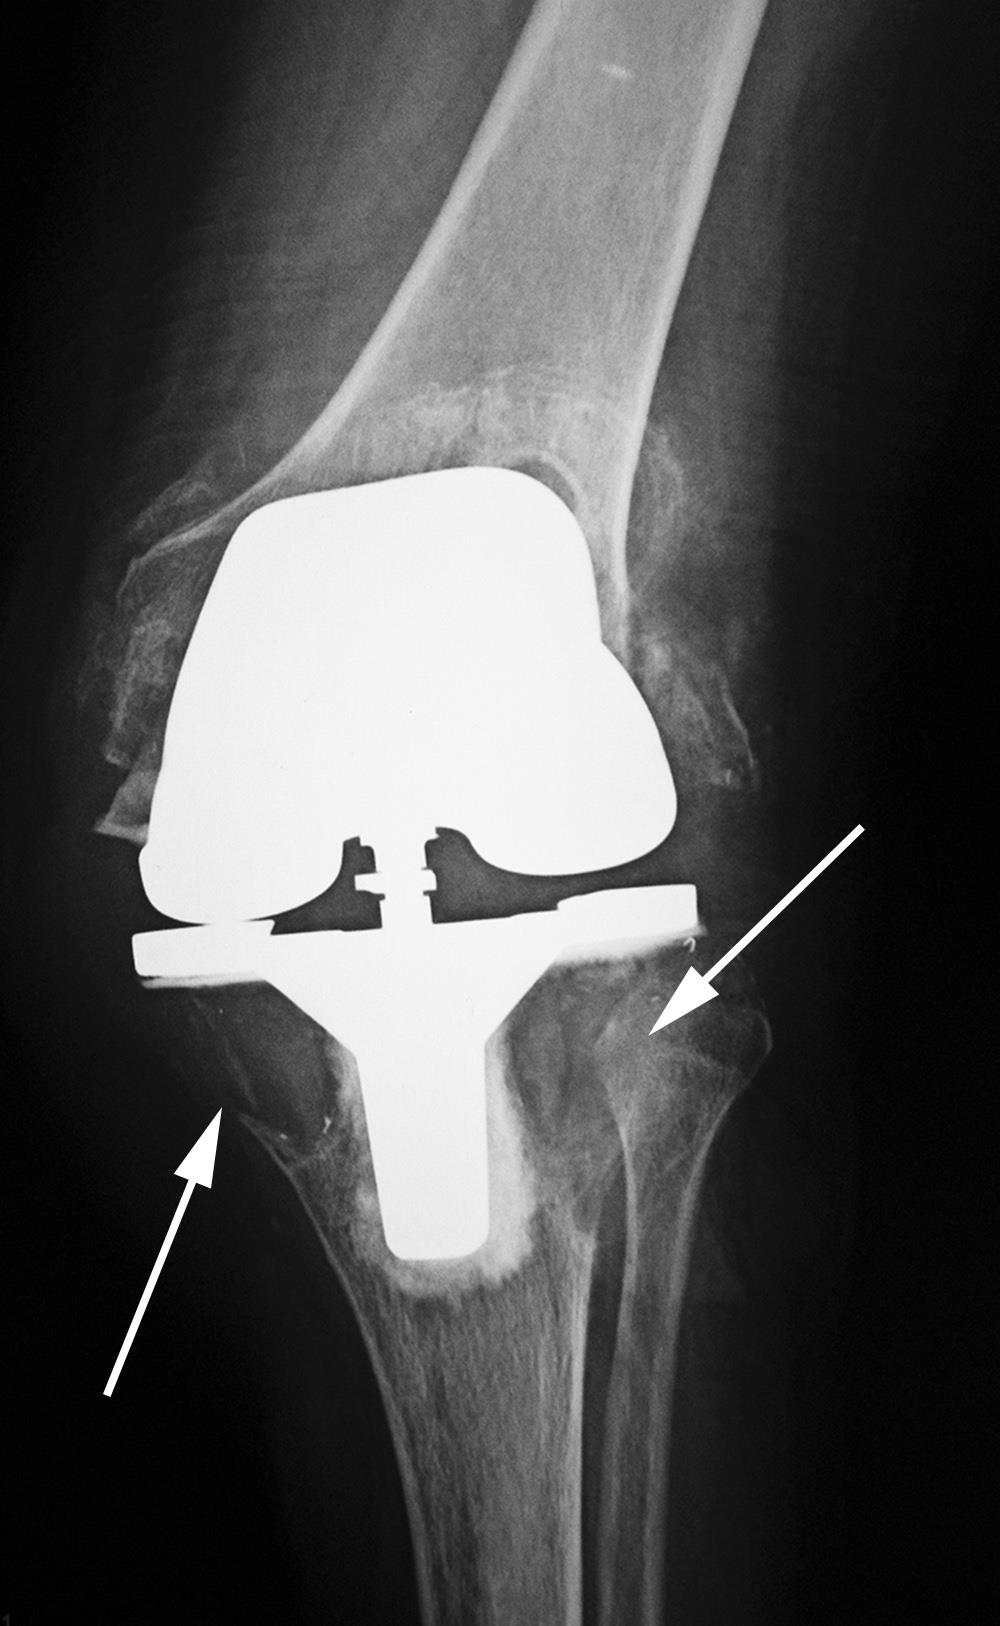

- Minimally invasive bone preserving Arthroplasty e.g. UKR (half a knee replacement)

The last option is a Total Knee Replacement. (Replacement of all 3 compartments – inside, outside and the front of the knee)

As I mentioned, I would love to perform hip and knee replacements all day, every day. I have some amazing state of the art equipment to utilise with and the results are terrific in the short to medium term. But what about the long-term? The need for further revision is required when the patient would be in their 60’s to 70’s, and there is only so much bone that can be removed before there are no options left.

A person in mid 60’s will be 75-80 years of age before his/her knee wears out. If you have followed my previous post – I have to resect some of your bone (not much with navigation technique) to replace it with metal and plastic.

This time the enemy is non-biological. The white cells in an attempt to kill the plastic will ingest (engulf) it but are unable to kill it and it the process the white cell releases all the toxic enzymes as it dies into the knee joint. These enzymes really have no effect on the metal or the plastic but it now starts to dissolve the bone behind the knee replacement and so the knee comes loose and the patient starts developing pain again.

This leads to revision knee replacement. The surgery is then repeated and the process starts all over again. If there is an active infection, sometimes this surgery takes place in two stages over a period of 6 – 12 months.

At some stage, there won’t be enough native bone to fix the revision knee into. This is a catastrophic disaster. The only option is a Tumor Prosthesis, which is not ideal and not indicated for the young.